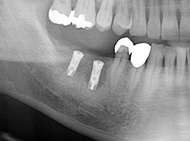

この患者さんは、歯根が割れてしまい、抜歯になってしまいました。

歯が真っ二つに割れて周りの骨が吸収して黒くなってしまっているのが分かります。

残念ながら抜歯をしてインプラントで対応することとなりました。

歯を抜いた周りの骨がしっかりと落ち着くまではしばらく待つことになりますが、